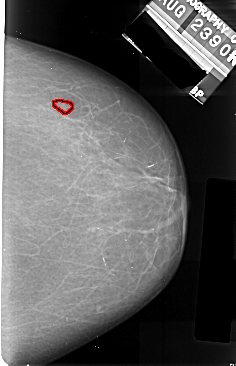

A_1005_1.RIGHT_MLO

RIGHT_MLO LINES 5176 PIXELS_PER_LINE 3646 BITS_PER_PIXEL 16 RESOLUTION 42 OVERLAY

FILE: A_1005_1.RIGHT_MLO.OVERLAY

TOTAL_ABNORMALITIES 1

ABNORMALITY 1

LESION_TYPE CALCIFICATION TYPE PUNCTATE DISTRIBUTION CLUSTERED

ASSESSMENT 4

SUBTLETY 2

PATHOLOGY MALIGNANT

TOTAL_OUTLINES 1

BOUNDARY